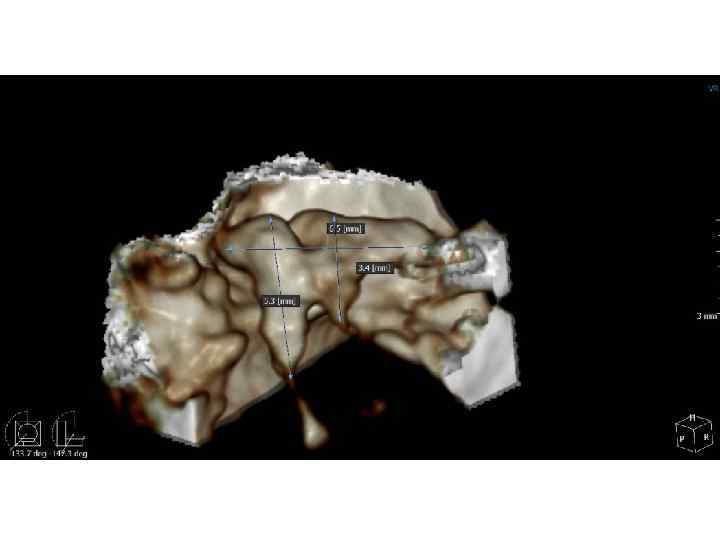

Выводы • Inobitec DICOM Weaver обладает возможностью 3 D-визуализации пирамиды височной кости, однако его Выводы • Inobitec DICOM Weaver обладает возможностью 3 D-визуализации пирамиды височной кости, однако его функции ограничены отсутствием необходимых программных инструментов. • Возможности КЛКТ в сочетании с Point. Nix Real. Scan позволяют проводить визуализацию мелких структур пирамиды височной кости.